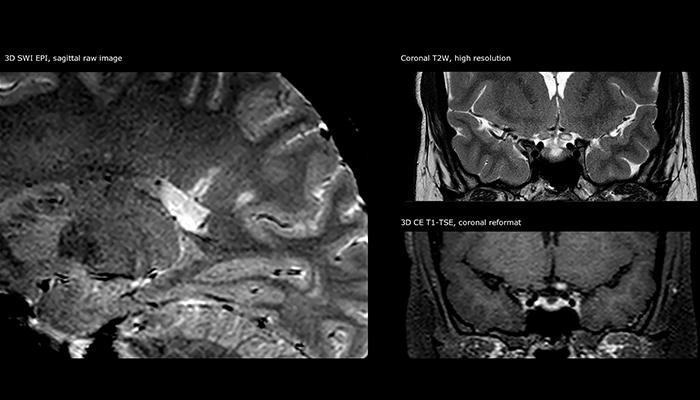

For MS imaging in the brain, Dr. Savatovsky uses 3D FLAIR as the basic sequence to visualize the lesions and assess the situation and lesion load. “We count the lesions in each location to determine if the criteria of the disease are fulfilled. We use a T2-weighted sequence because our neurologists are used to it. We compare the lesion load on FLAIR with a 3D T1 post-contrast sequence to help us determine whether lesions are old or new. We typically administer the contrast before the patient enters the machine because it shortens the examination time and allows to visualize active lesions that tend to be more visible after several minutes. When a differential diagnosis is difficult, we add sequences such as susceptibility imaging, because some focal MS lesions have a small vein in the center[3].”

“For MS imaging in the spine, the basic examination includes a sagittal T2 and a post-contrast sagittal T1-weighted sequence in the whole spine. These are done in two stacks and using thin slices, for example 2 mm, without gap. As in the brain, the T2-weighted sequence visualizes the overall lesion load and helps determine if lesions are old or new. The post-contrast T1- weighted sequence helps in assessing if a lesion is new. We will sometimes add a T1 inversion recovery sequence, which has very good sensitivity, if we don’t find any lesions on T2,” Dr. Savatovsky says. “Additionally, if there is contrast enhancement outside the spine, it’s usually not MS but another kind of inflammation.”